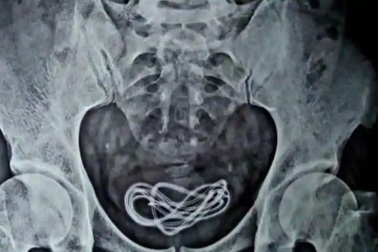

Mắc kẹt dây sạc điện thoại dài 70 cm trong bàng quangBác sĩ choáng váng khi một vật như dây sạc điện thoại lại có thể kẹt trong bàng quang của người đàn ông tới 5 ngày.